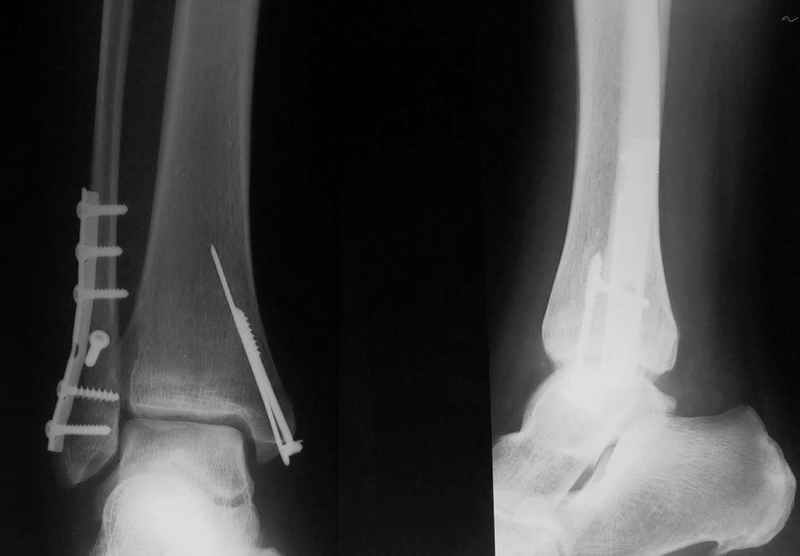

Ответы на вопросы: 1. Дистракцию снять! Все правильно вы понимаете: наружная лодыжка -ключ г\ст сустава, а пытаетесь наоборот - таранную кость сделать "ключом"... Нейротрофические расстройства очень могут появиться..

2. Конечно аппарат собран не лучшим образом. База на стопе очень низко расположена, есть даже сомнения: обе ли спицы проходят через пяточную кость? Откройте любое руководство по чрескостному остеосинтезу и найдете ответ на вопрос, как компоновать аппарат, возможно, даже удивитесь, когда узнаете , что есть компановки вообще не фиксирующие г\ст сустав.

3. Если добиваться в аппарате, то только путем проведения дополнительных спиц и небольшого перемонтажа... Диастаз говорит только о неанатомичной репозиции лодыжки, со всеми вытеающими...

Вообщем, еще не поздно (и совершенно неопасно) снять аппарат, и сделать открытую репозицию и полноценный остеосинтез наружной лодыжки стягиваающим винтом и нейтрализующей 1\3-трубчатой пластиной... Лучше это было сделать сразу при поступлении в качестве экстренной операции, крнечно если есть возможность, а она всегда будет, если есть желание!!

Стабильность г\ст сустава обеспечивается во-первых наружной лодыжкой (ключ), во-вторых задним краем б\б кости, в-третьих связками синдесмоза и межкостной мемраной, только в-четвертых медиальной лодыжкой (дельтовидной связкой. Это классика! А пяточной кости и плюсневых костей здесь нет! зачем их фиксировать? см. вложенный файл.

Коллега!Sorry,по-моему стоит провести винт через синдесмоз,а?Вроде бы контуры г\ст не совпадают,нет?Я дал бы компрессию на синдесмоз в положении полного разгиба стопы

1. Винт никогда не стоит проводить "через" синдесмоз. Если и проводить, то выше синдесмоза.

2. Межберцовый винт должен быть только позиционным и должен удерживать синбесмоз, а не компремировать его

3 Контуры девственны: талокруральный угол, суперпозиция, медиальное пространство. Что не совпадает?

Вообще, этот больной через 2 месяца после травмы в футбол играл.